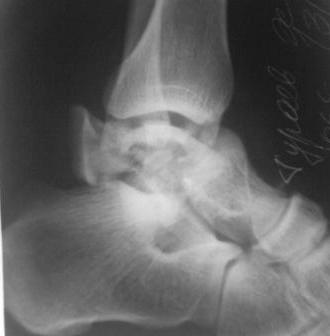

Осколчатый перелом таранной кости

Поступил б-ной, 1965г.р., вчера упал с высоты. В травм. пункте произведена репозиция. наложена гипсовая повязка.

Обратился с сильными болями в стопе, срочно рассечена гипсовая повязка, выраженный отек стопы, сплошные фликтены, конечность уложена на шину Белера, скелетное вытяжение за пяточной кость, антибиотики, анальгетики, клексан, трентал.

1.Сразу готовится к артродезу?

2.Или постараться открыто собрать осколков?(тогда вероятность асеп.некроза большая)

3.Дистракцион.остеосинтез А.В.Ф.,и дальше время покажет?